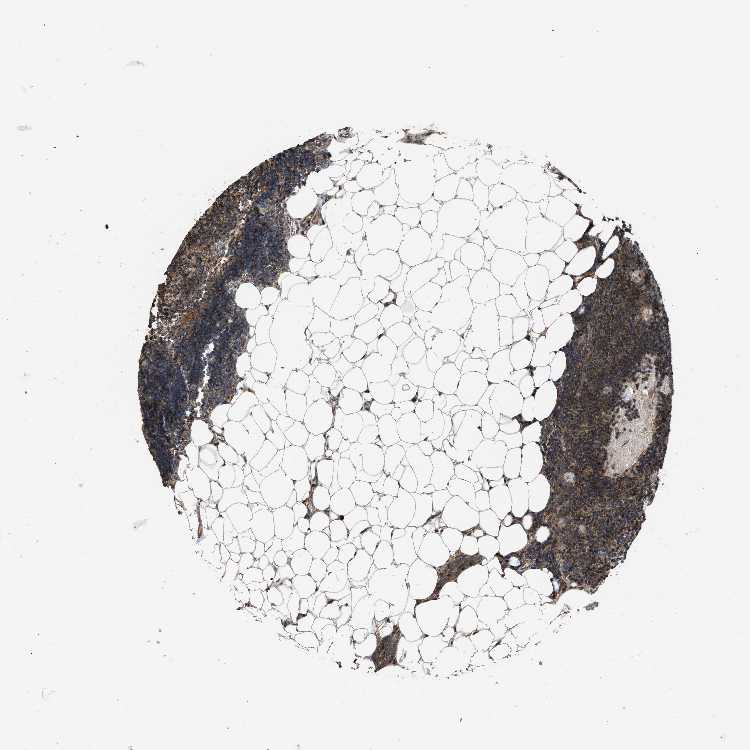

TISSUE PRIMARY DATA LYMPH NODE Show tissue menu

Lymph node

LYMPH NODE - Antibody stainingi

Antibody staining in the annotated cell types in the current human tissue is reported as not detected, low, medium, or high, based on conventional immunohistochemistry profiling in selected tissues. This score is based on the combination of the staining intensity and fraction of stained cells.

Each image is clickable and will lead to virtual microscopy that enables deeper exploration of all samples and also displays staining intensity scores, fraction scores and subcellular localization as well as patient and tissue information for each sample.

Antibody HPA009985Antibody CAB017804

Non-germinal center cells MediumHigh